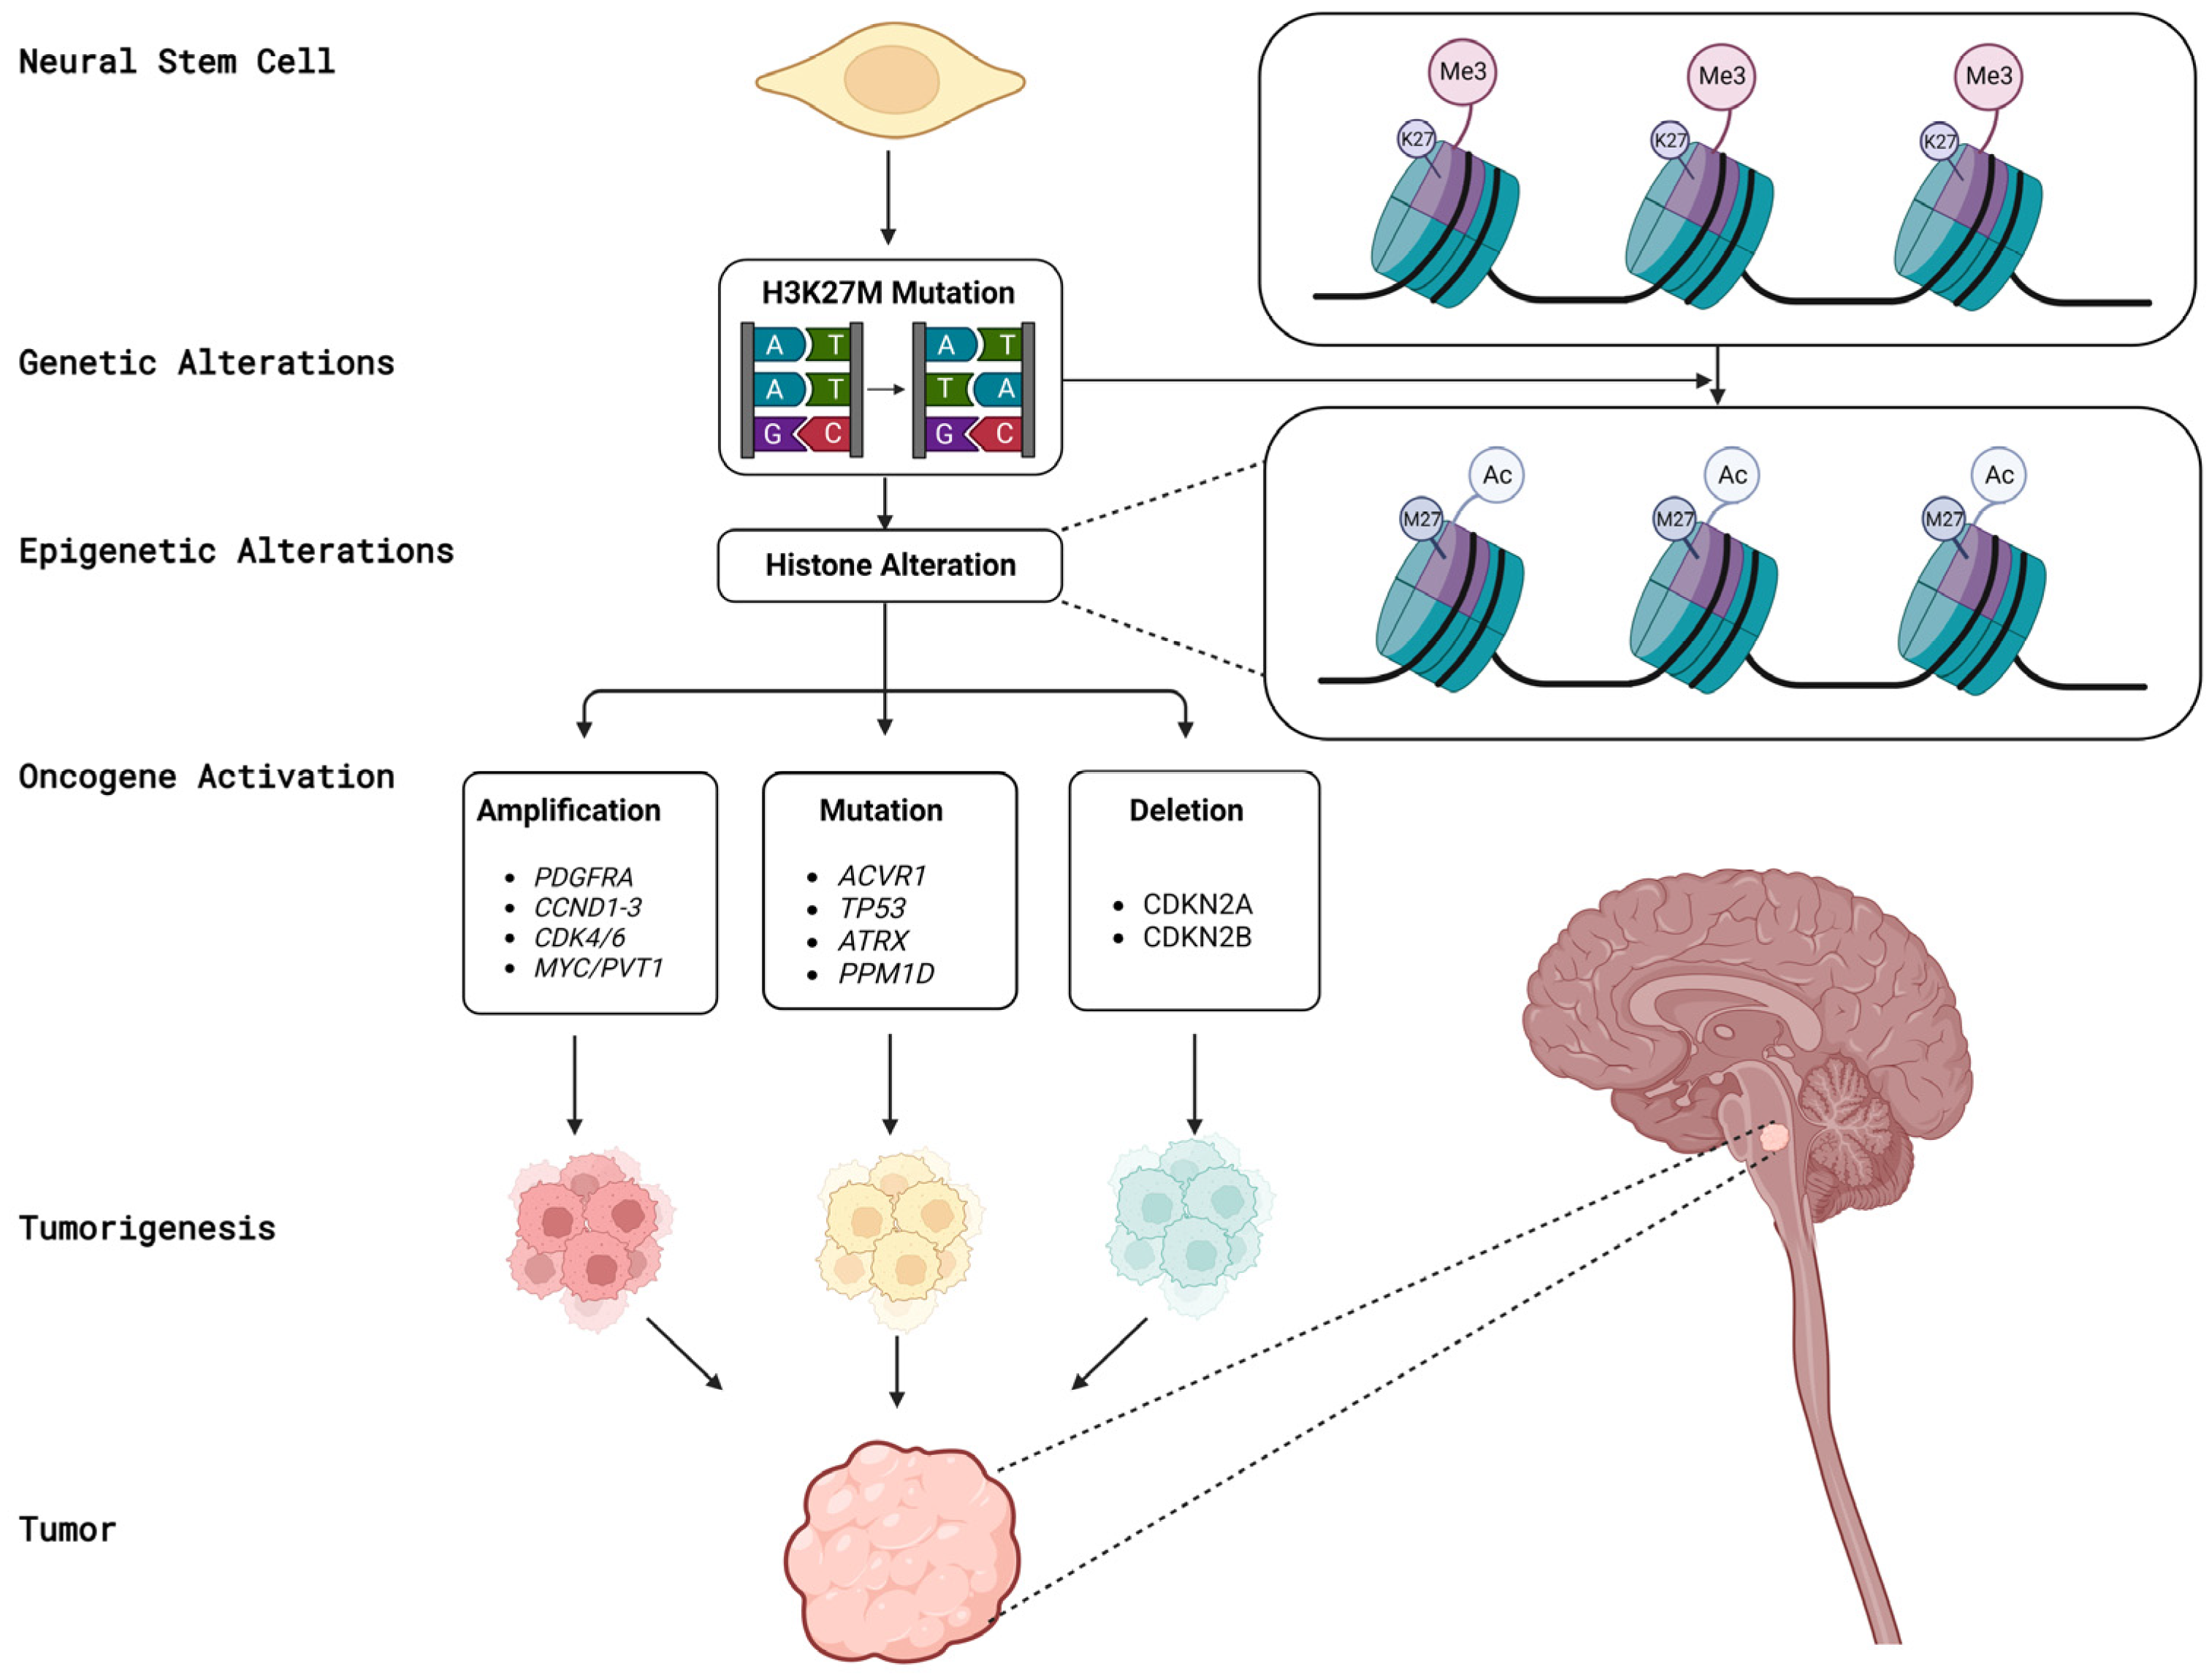

3. Biological Aspects of DMGs